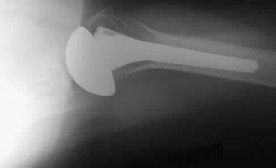

A 72-year-old female undergoes a reverse total shoulder arthroplasty (rTSA) for severe rotator cuff tear arthropathy. Compared to the native anatomic shoulder, which of the following best describes the biomechanical alteration of the center of rotation following a standard Grammont-style rTSA?

Explanation

Question 22

Scapular notching is a well-recognized complication following Reverse Total Shoulder Arthroplasty (RTSA). Based on modern biomechanical principles and implant design modifications, which of the following component positioning strategies is most effective in minimizing the risk of inferior scapular notching?